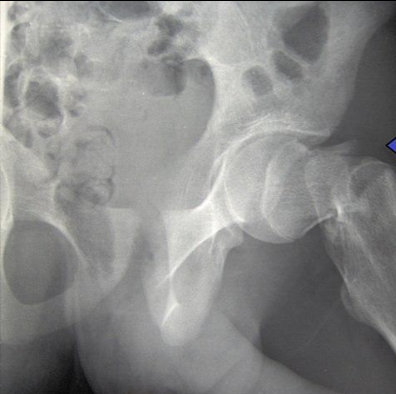

A

Fx cuello femoral

Fx intertrocanterica